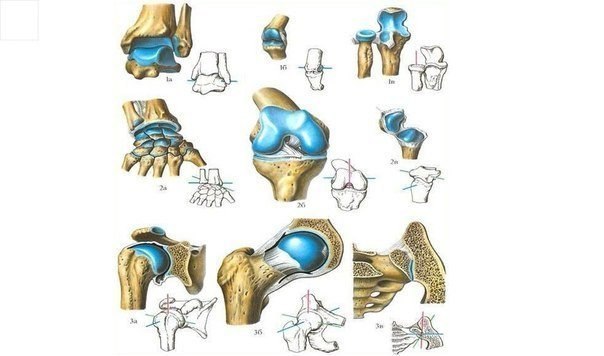

Проблемы заболеваний суставов в спорте сводятся к истиранию хрящевой ткани, покрывающей скользящие поверхности суставов. Вообще — то, хрящи сами по себе очень прочны, а потому истирание постигает суставы где — то глубоко за семьдесят. Однако когда вы, к примеру, приседаете с тяжелой штангой, вес отягощения «припечатывает»суставные поверхности друг к другу с силой, на которую природа не рассчитывала.Трение внутри коленного сустава многократно возрастает, отсюда и берется преждевременное истирание.

Профилактика этого явления сводится к приему препаратов, препятствующих истиранию или восстанавливающих состоявшиеся повреждения.